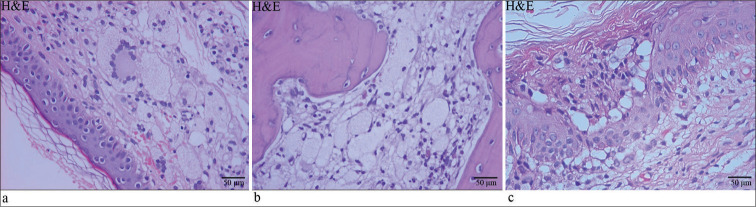

Langerhans cell histiocytosis (LCH) and Erdheim-Chester disease (ECD) are exceptionally rare disorders characterized by varied clinical presentations, posing several challenges for clinicians. The concomitant occurrence of LCH and ECD is exceedingly rare and has no known etiology. In this report, we present a rare case of mixed histiocytosis (both ECD and LCH) with multisystem involvement. The patient, a 49-year-old female, initially presented with a rash 2 years ago and progressively developed exophthalmos, fatigue, and shortness of breath. She lacked the mutation in codon 600 of exon 15 of B-Raf proto-oncogene (BRAF-V600E) and subsequently underwent treatment with corticosteroids, interferon-alpha, and chemotherapy, all of which proved ineffective. This work highlights the urgent need to improve treatment outcomes for such patients. Therefore, we discuss the latest advancements in understanding treatment strategies for mixed histiocytic syndromes.